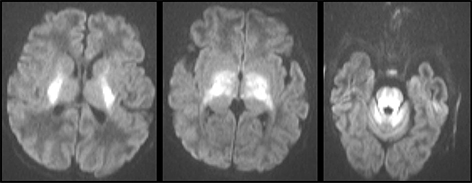

Fig 11

Figure 11. A 20-day-old boy with classic-type of maple syrup urine disease (MSUD). Axial DWI images showing symmetric pattern of acute restricted diffusion in the basal ganglia, thalami, brainstem, characteristic of exacerbation of MSUD. Case courtesy of Dr. Tamara Feygin, Department of Radiology, Children’s Hospital of Philadelphia.